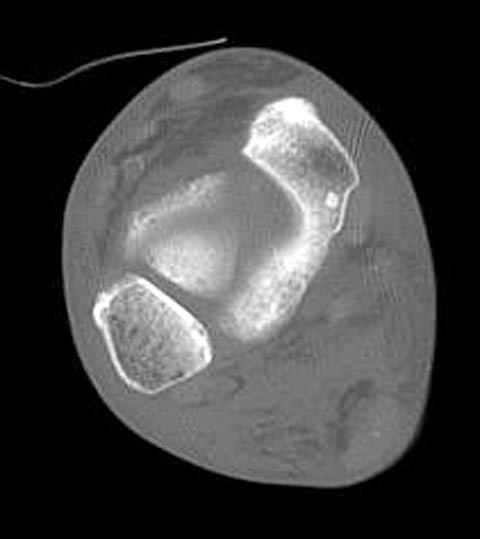

из

Уважаемые участники русского Ортофорума, поздравляю всех со всеми прошедшими праздниками: Новым годом, Рождеством, Hanukkah, Kwanzaa, желаю участникам всего наилучшего и здоровья. Повреждение таранной кости. Больной 81г автоавария, повреждение таранной кости, здесь снимки.

Какие рекомендации? Djoldas Kuldjanov, MD Department of Orthopedic Surgery St. Louis University Medical Center